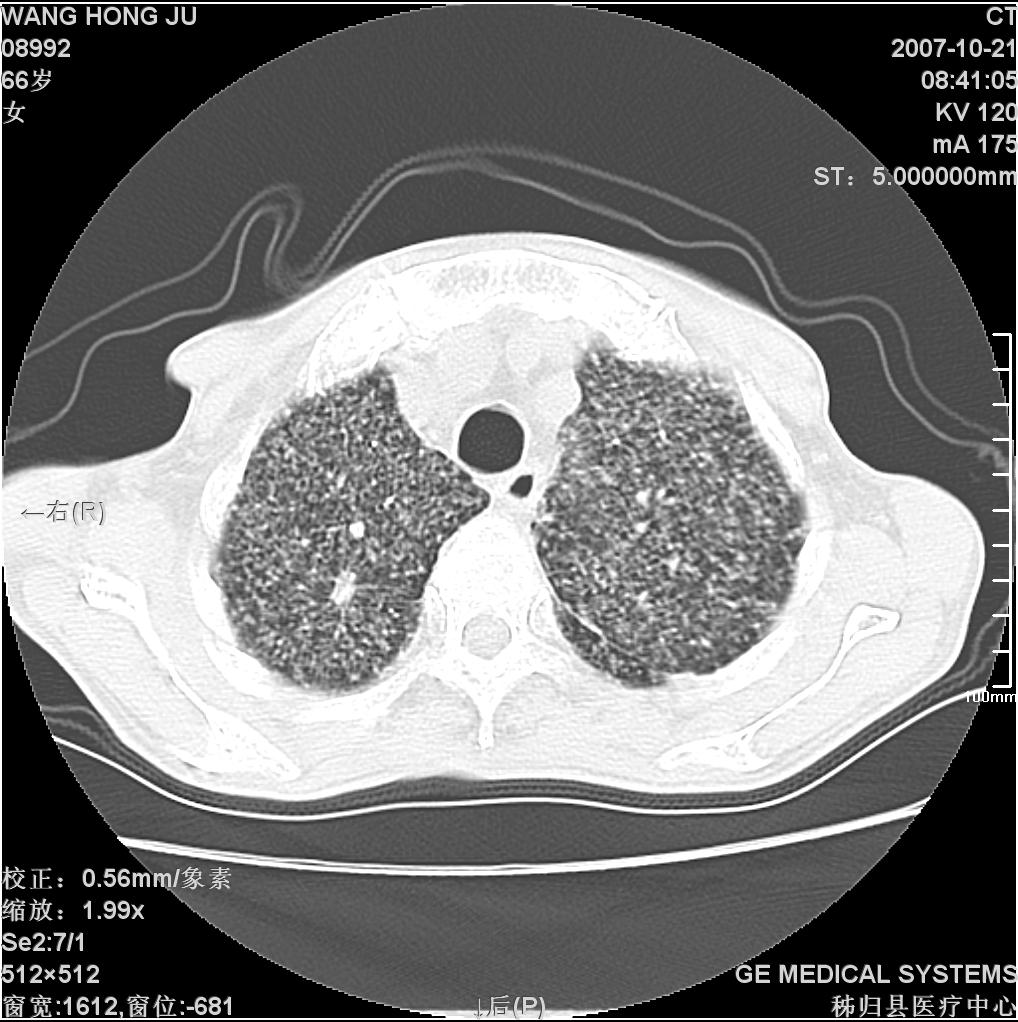

患者咳嗽月余,高热数天,咳黄色稍脓痰。

双肺野分布多个小结节状高密度影,其内散在斑片状模糊影,气管。支气管通畅,纵隔内淋巴结钙化,胸膜局限性增厚粘连,胸腔少量积液。结合病史考虑结核并感染的可能性大,胸膜炎并积液。肺泡癌待排。

亚急性血行播散型肺结核合并肺内感染

纵隔内见钙化的淋巴节,上肺见钙化灶,双肺均匀弥漫分布小结节影,边缘较清楚,能不能考虑是在矽肺的基础上并发的结核和感染,请详细了解病史结合临床.